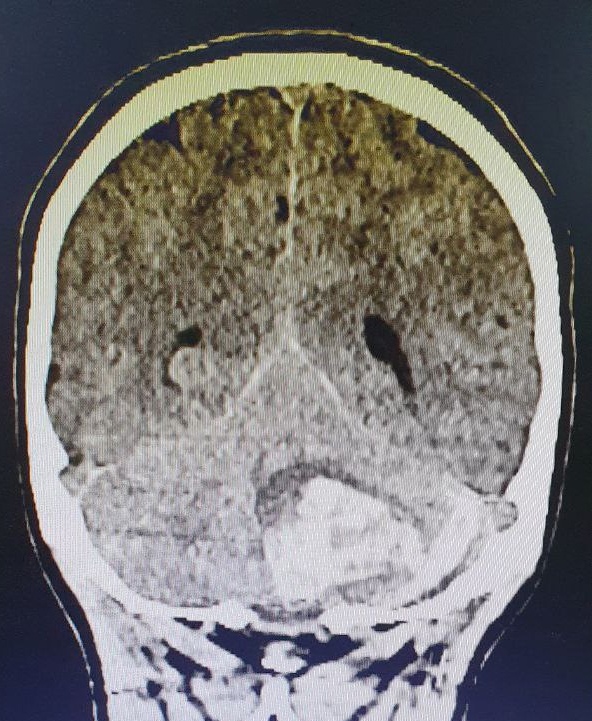

Нижегородские хирурги спасли 15-летнюю пациентку с инсультом, сообщается на странице Областной детской клинической больницы в соцсетях.

Девушка почувствовала себя плохо еще дома. У нее заболела голова, появились судороги и нарушение сознания. Медики доставили пациентку в НОДКБ, где во время КТ мозга врачи диагностировали кровоизлияние. С подозрением на спонтанный разрыв сосудов девушку госпитализировали в отделение реанимации.

По словам врачей, на принятие решения о тактике лечения оставались считанные часы. Через сутки после госпитализации нейрохирурги НОДКБ совместно с сосудистым хирургом Городской клинической больницы № 13 Анатолием Шелудяковым успешно удалили внутримозговую и субдуральную гематомы мозжечка, также удалена сосудистая мальформация.

«Об этой коварной аномалии развития пациенты часто не знают до наступления сосудистой катастрофы. Спонтанно развившееся кровоизлияние наступает из-за разрыва артериовенозной мальформации — „сосудистого клубка“ из переплетенных вен и артерий», — сообщил врач-нейрохирург НОДКБ Дмитрий Кирин.

Медики сообщают, что пациентка уже переведена из реанимации в нейрохирургическое отделение, динамика положительная, ей разрешили сидеть в кровати. Девушке предстоит курс реабилитации и МСКТ-ангиография для исключения других патологических сетей сосудов головного мозга.

По словам врачей, подобные кровоизлияния диагностируются крайне редко, не более двух случаев в год.